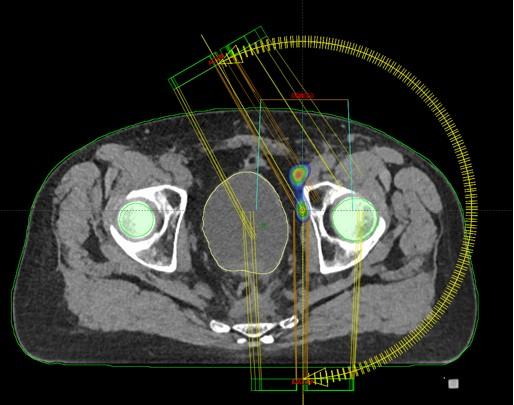

Prostata

Bolesnik, rođen 1951.